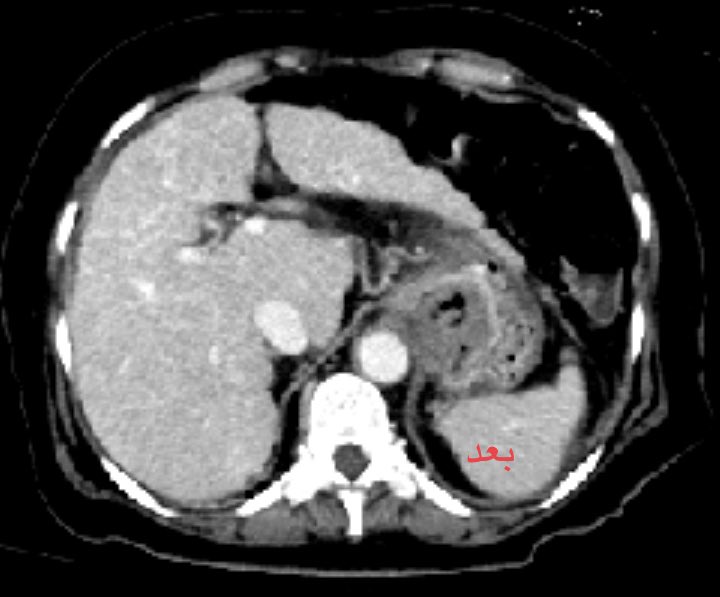

#MASLD #cirrhosis with GI bleeding, PVT not improving on heparin despite large acute component developed over 3 wks. ICE TIPS with subsequent asp vs thrombectomy established flow. #VIRad #GItwitter #livertwitter #meded #FOAMed

English